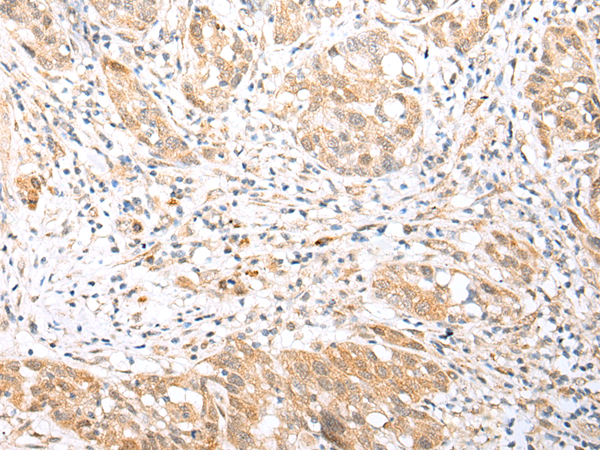

IHC positive control: |

Human thyroid cancer and human gastric cancer |

IHC Recommend dilution: |

25-100 |